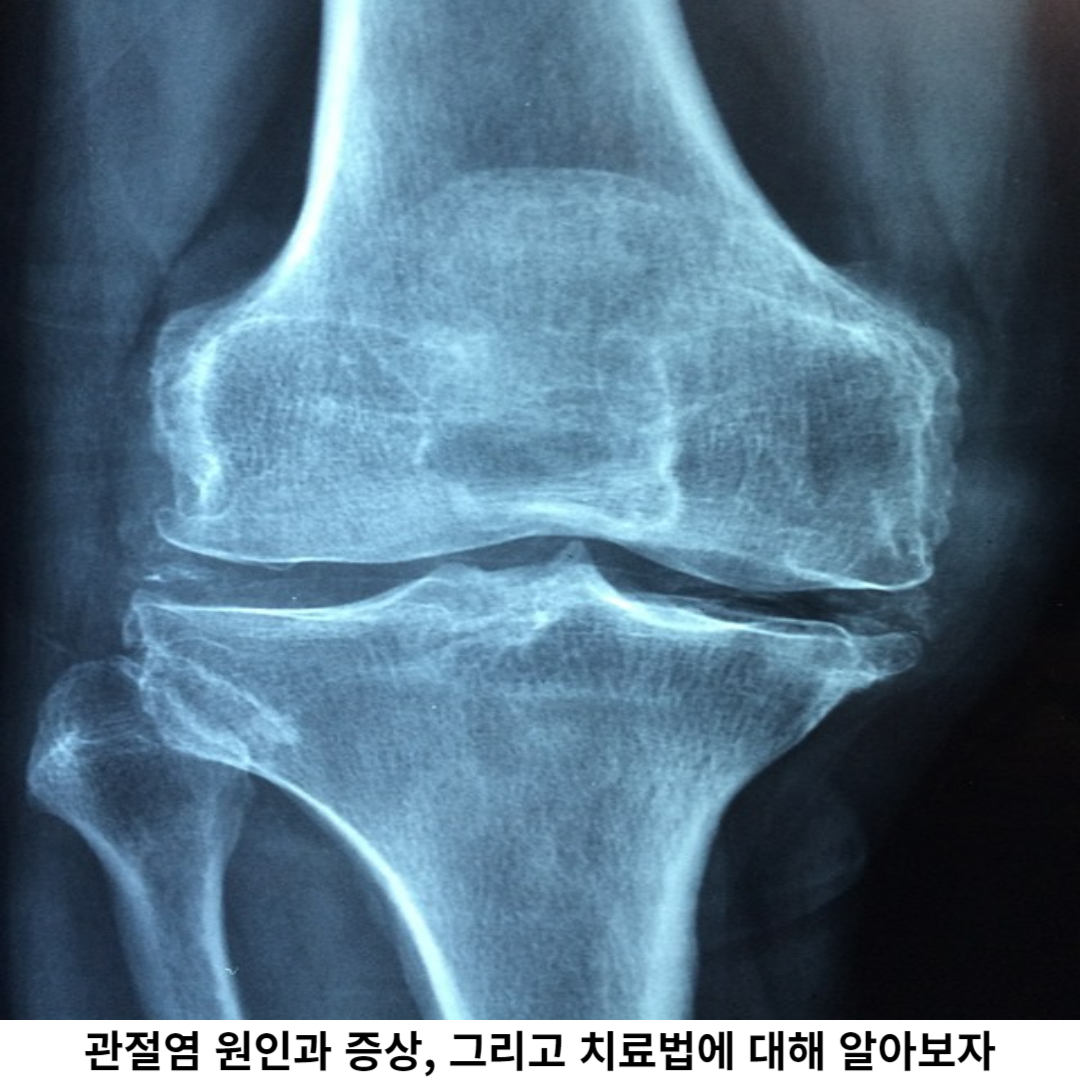

관절 부종은 염증으로 인해 관절 주변 조직에 비정상적인 액체가 증가되는 현상을 의미합니다. 이는 관절의 부흥연골에 압력을 가하고 통증을 유발하여 환자에 고통이 증가합니다.

부종은 관절의 운동 범위를 제한하고, 관절 주변의 부력을 증가시켜 더 많은 통증이 발생됩니다. 강직성은 관절의 움직임에 제한이 있는 상태를 의미합니다. 초기 단계에서는 관절의 강직성이 적지만, 진행되면서 점점 심해질 수 있습니다.

관절을 움직일 때 뻣뻣한 느낌이 들며, 활동 범위가 좁아지는 것을 경험할 수 있습니다. 관절의 운동 제한은 일상생활 활동에 지장을 초래하며, 움직임에 저하로 이어질 수 있습니다.

기능 장애는 관절의 염증과 손상으로 인해 기능이 제한되는 것을 의미합니다. 예를 들어, 손목 관절 염증으로 인해 물건을 잡거나 손을 움직이는 것이 어려울 수 있습니다.

무릎 관절 염증으로 인해 앉았다 일어나는 것이 힘들어질 수 있으며, 발목 관절 염증으로 인해 걷기가 매우 힘들어집니다. 이러한 기능 장애는 개인의 삶의 질을 저하시키고 심리적 위축감마저 발생되어, 일상 활동이 어렵게 됩니다.